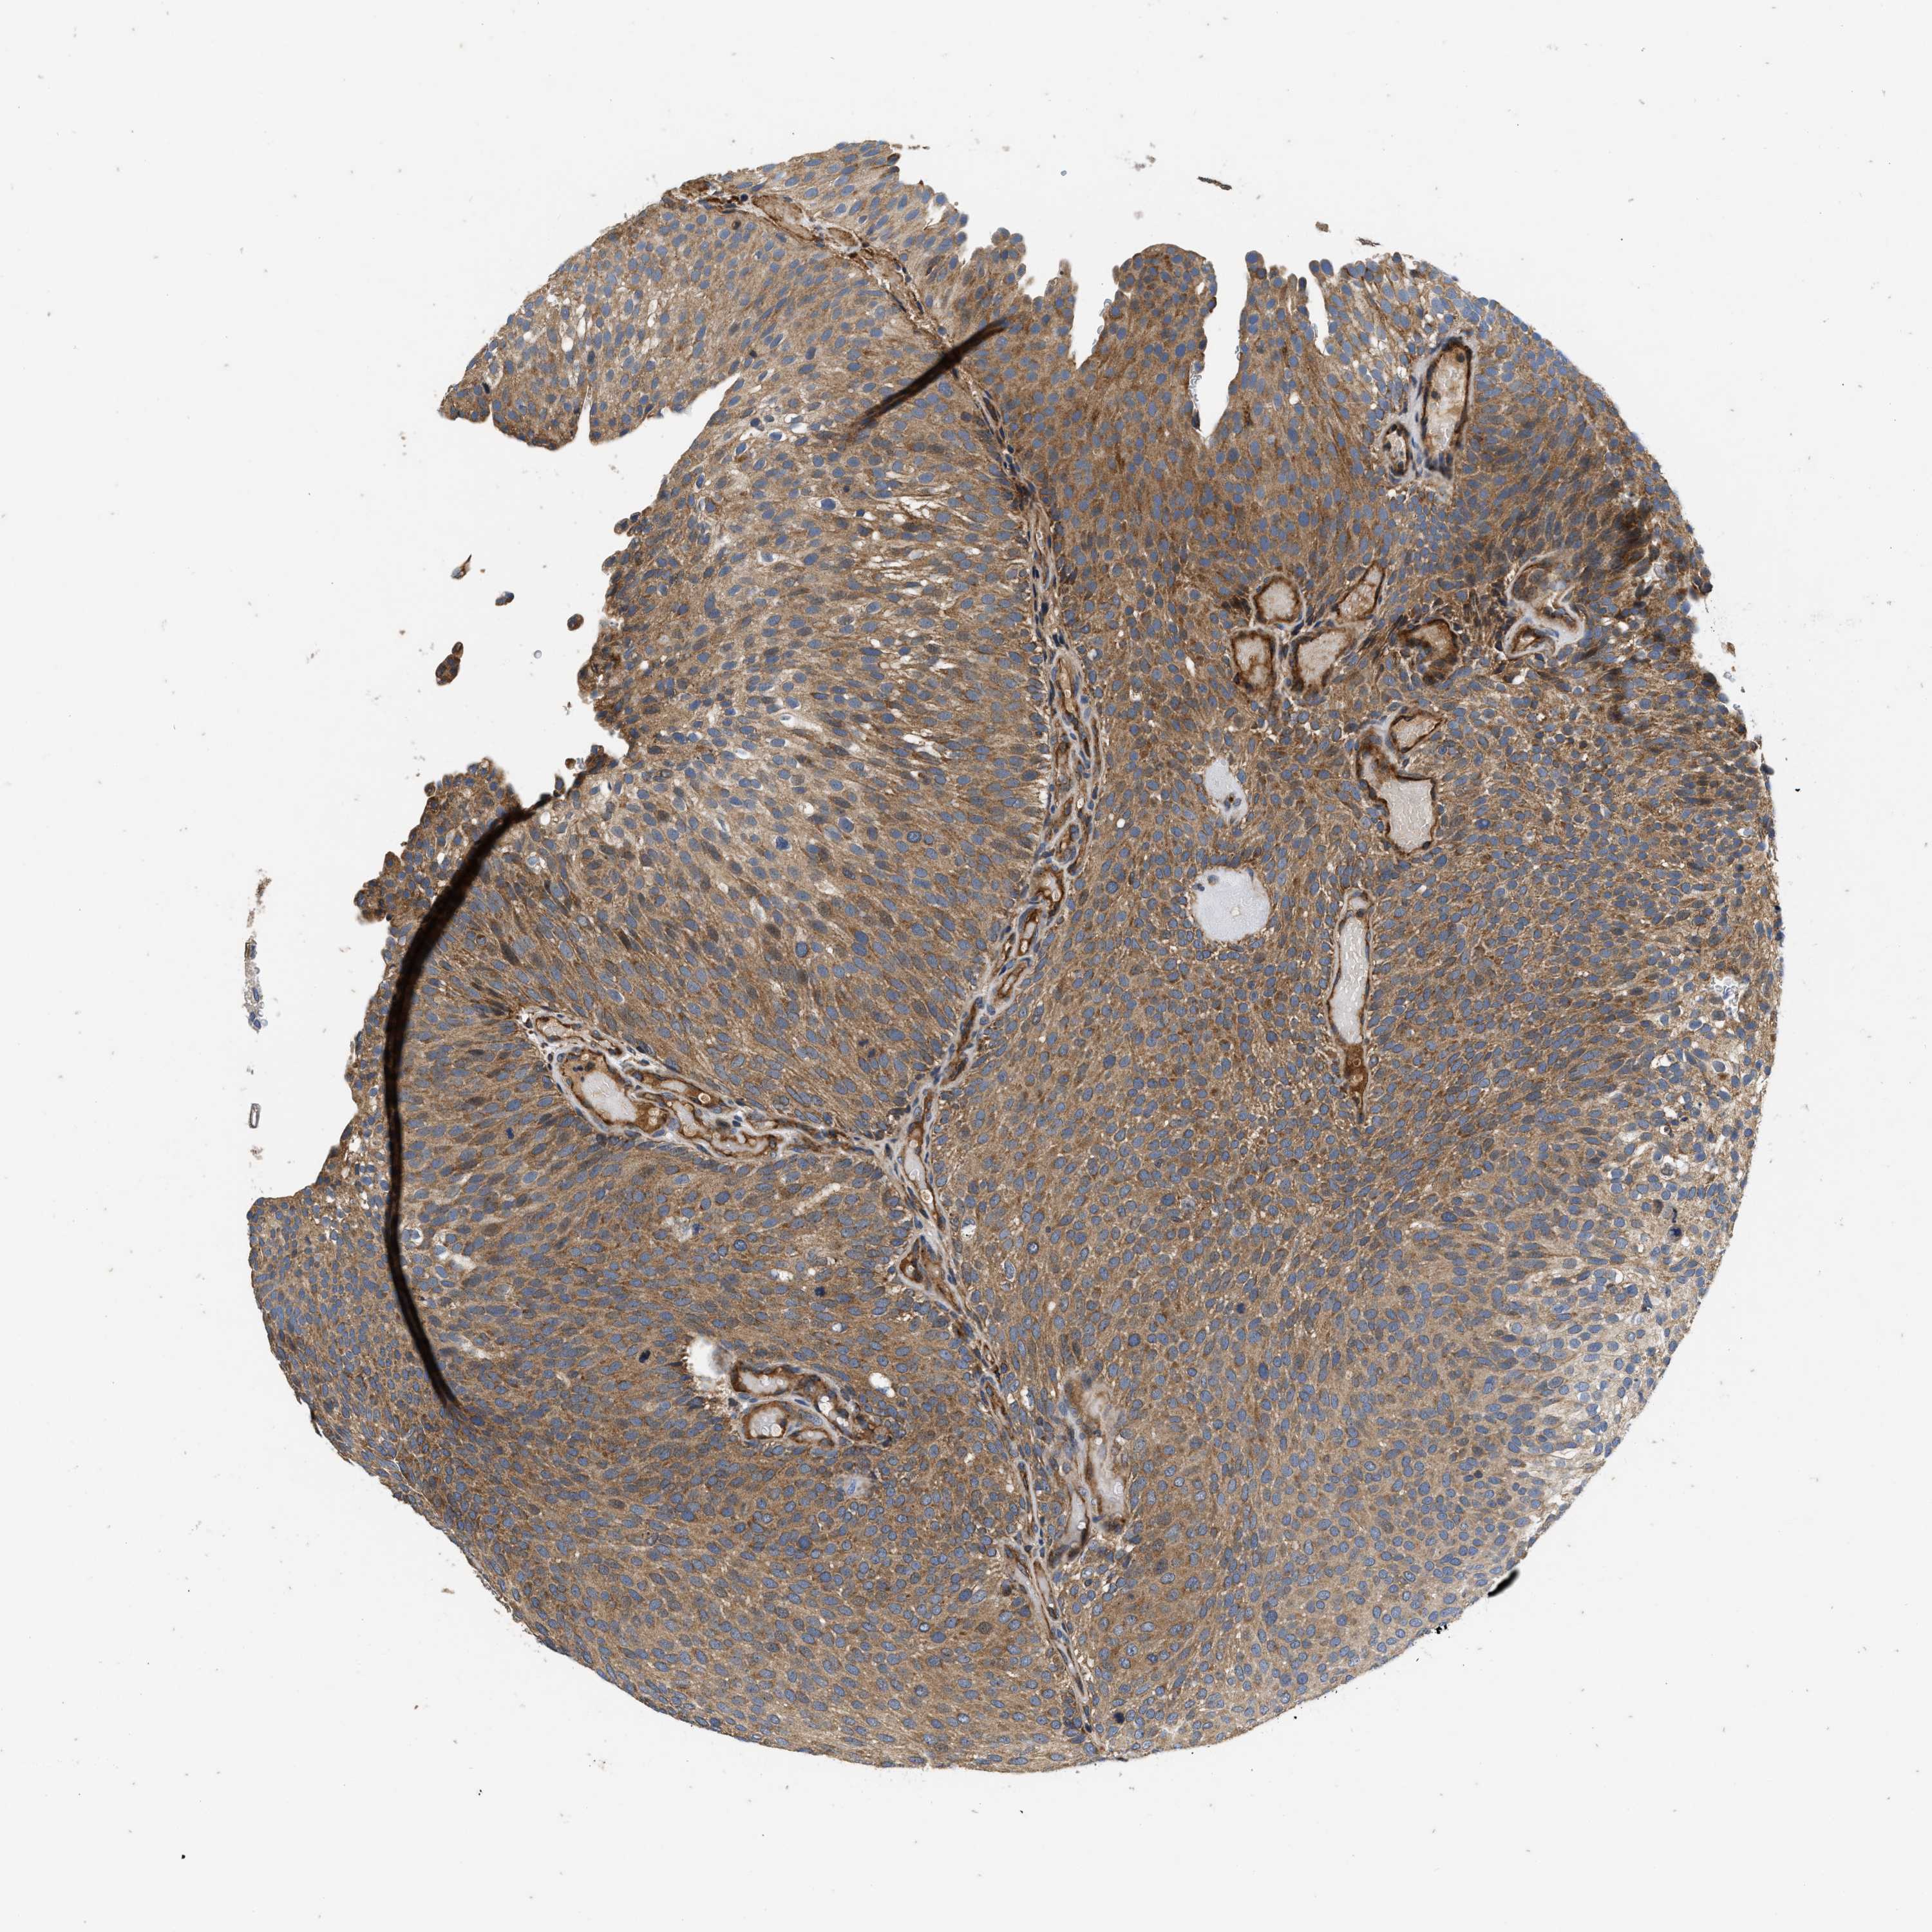

UROTHELIAL CANCER - Protein expressioni

A mouse-over function shows sample information and annotation data. Click on an image to view it in a full screen mode. Samples can be filtered based on level of antibody staining by selecting one or several of the following categories: high, medium, low and not detected. The assay and annotation is described here.

Antibody stainingi

Antibody staining in the annotated cell types in the current human tissue is reported as not detected, low, medium, or high, based on conventional immunohistochemistry profiling in selected tissues. This score is based on the combination of the staining intensity and fraction of stained cells.

Each image is clickable and will lead to virtual microscopy that enables deeper exploration of all samples and also displays staining intensity scores, fraction scores and subcellular localization as well as patient and tissue information for each sample.

Antibody HPA017909

Staining

High

Strong

>75%

Cytoplasmic/membranous

Urothelial carcinoma, High grade